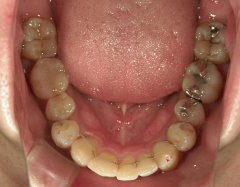

矯正歯科 治療後矯正歯科 全顎ワイヤー矯正 治療後矯正歯科(全顎ワイヤー矯正)治療後

矯正歯科 治療後 E-AMXというセラミックにて左右上1番を被せ直しました。